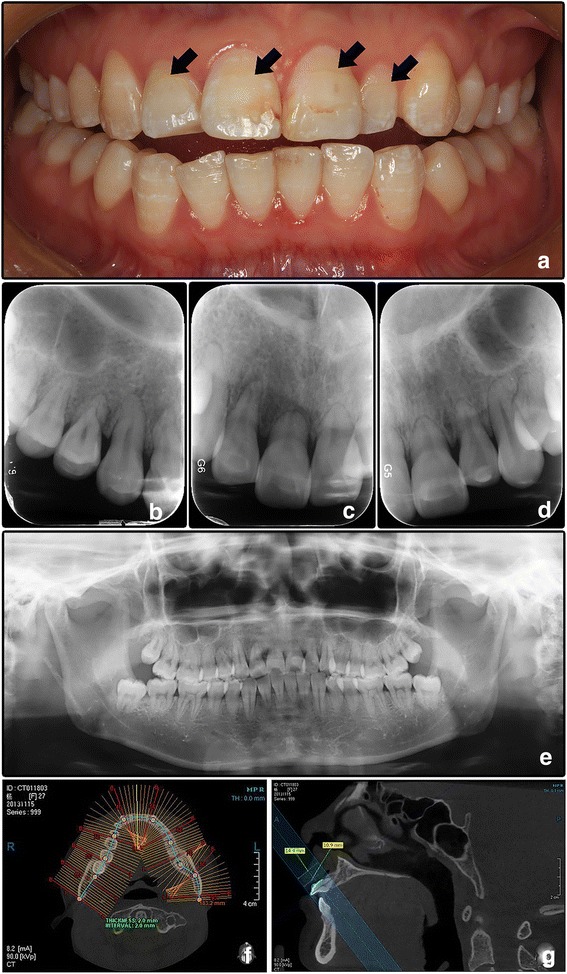

A 27-year-old female Chinese patient presented with looseness of her maxillary incisors (teeth #11 and #12) was treated with an arch bar from tooth #14 to tooth #22 for 5 months in outside institution. She then suffered from upper incisors pain and was referred to us. The patient was 160 cm height and 46.5 kg weight, with a Body Mass Index (BMI) of 18.2 (normal range 18.5–23.9). She also had mild symptoms of heat intolerance, anxiety, polyphrasia, tremor, palpitate, chest tightness, anhelation, and muscle aches. The patient had a history of premature loss of some deciduous teeth in childhood. The family history was unremarkable. Physical examination revealed mild goiter and exophthalmos. Intraoral examination found pale spots on the crowns due to mild enamel hypoplasia (Fig. 1a). No tender to percussion, and no tooth mobility after removal of the arch bar.

Fig. 1.

Clinical and imaging manifestation of Case 1. a Frontal intraoral view shows the teeth crowns appear normal except for several spots due to mild enamel hypoplasia. b-d Periapical radiographs show the short root anomaly of the maxillary incisors. e Panoramic film. f-g Teeth lengths were measured by CBCT

Periapical and panoramic radiographs showed that the roots of all teeth were short (Fig. 1b-e).CBCT scan (Fig. 1f, g) proved that the lengths of all the roots (except for four 3rd molars) were shorter than normal, whereas the crowns lengths were broadly within the normal range (Table 1). Chest X-ray and skeletal radiographs of upper and lower limbs didn’t show any significant changes. The laboratory analyses of urinalysis, complete blood count, serum calcium level, serum CT level, and PTH level were normal. Serum ALP level was 59.0 U/L (normal range 45.0–125.0 U/L). Unexpectedly, serum TSH level was lower than 0.011 uIU/mL (normal range 0.270–4.200 uIU/mL), serum FT3 7.52 pmol/L (normal range 3.10–6.80 pmol/L), and serum FT4 18.33 pmol/L (normal range 12.00–22.00 pmol/L).